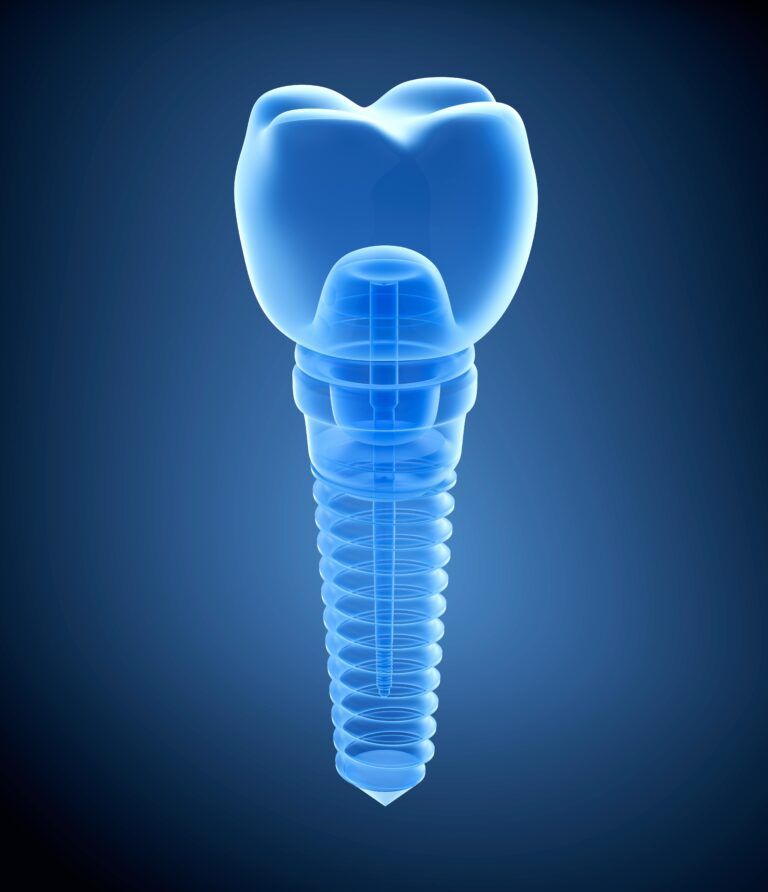

The 3 Parts of Dental Implants and What They Do

At a glance, dental implants offer a variety of benefits for individuals looking to replace one or more missing teeth. However, to truly understand why dental implants are the gold standard of tooth replacement options, we need to take a

Endosteal Implants: The Standard in Implant Dentistry

Dental implants have revolutionized the way we approach the restoration of missing teeth, offering solutions that are not only functional but also aesthetically pleasing. Among the various types of dental implants available, endosteal implants stand out as the most commonly

Understanding Dental Implants: A Comprehensive Overview

Dental implants have revolutionized restorative dentistry, offering a durable and aesthetically pleasing solution for missing teeth. But what exactly are dental implants, and how do they work? This blog aims to provide a comprehensive overview of dental implants, from their